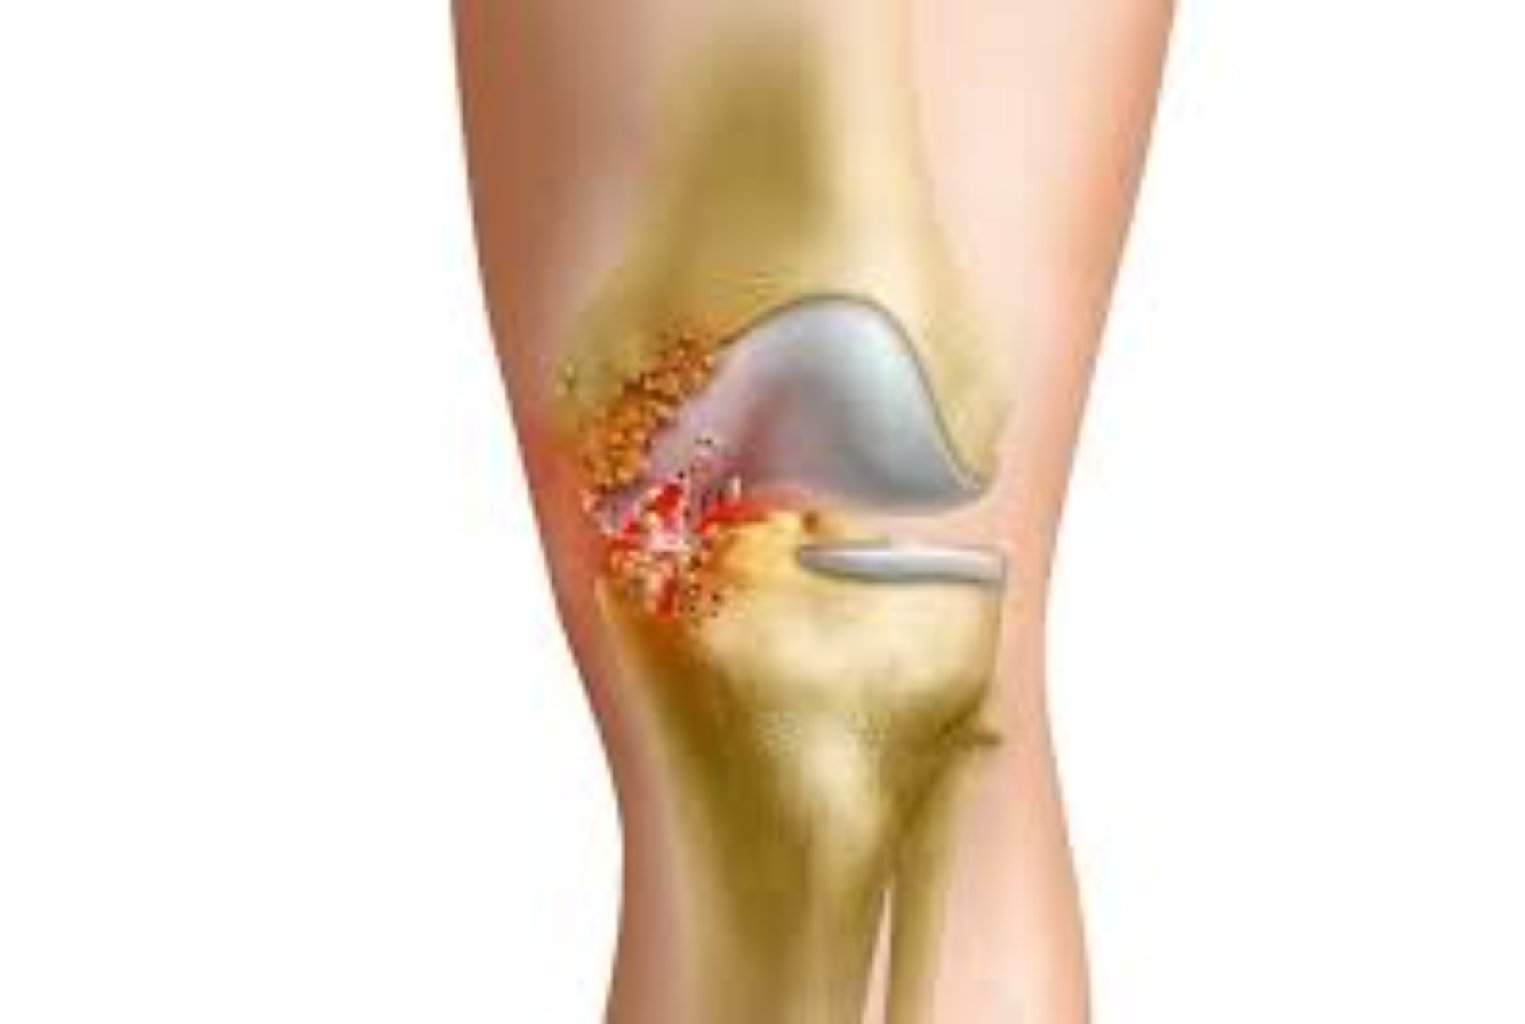

Menisk yırtığının səbəbləri Travma: Ani Dönmə və Dayanma: Futbol və basketbol kimi idmanlarda ani dö ...